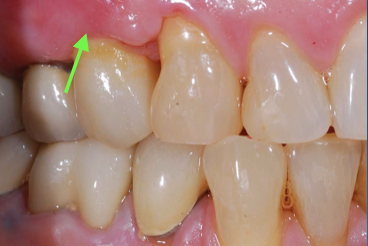

(14.) Healthy Gingival Tissue.

Figure 14